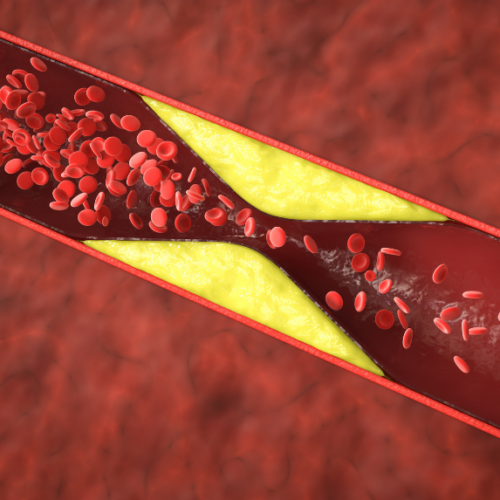

La cardiopatía isquémica y su tratamiento

El origen de la cardiopatía isquémica está en un cúmulo de grasa a nivel de la arteria coronaria: se rompe, produce un trombo que evita el paso de sangre hacia el músculo cardíaco.